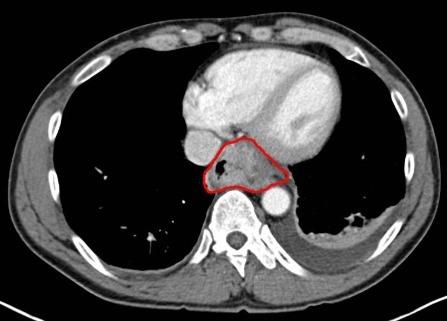

CT 및 PET 스캔:

흉부 및 복부 CT 스캔과 PET 스캔을 통해 암의 전이 여부를 확인합니다. 이 검사는 식도암이 주변 조직으로 전이되었는지를 평가하는 데 중요합니다.

- 원발종양(T): 암이 식도벽을 얼마나 침범했는지를 평가합니다.

- 국소림프절전이(N): 림프절의 침범 여부를 확인합니다.

- 원격전이(M): 다른 장기로의 전이 여부를 판단합니다.